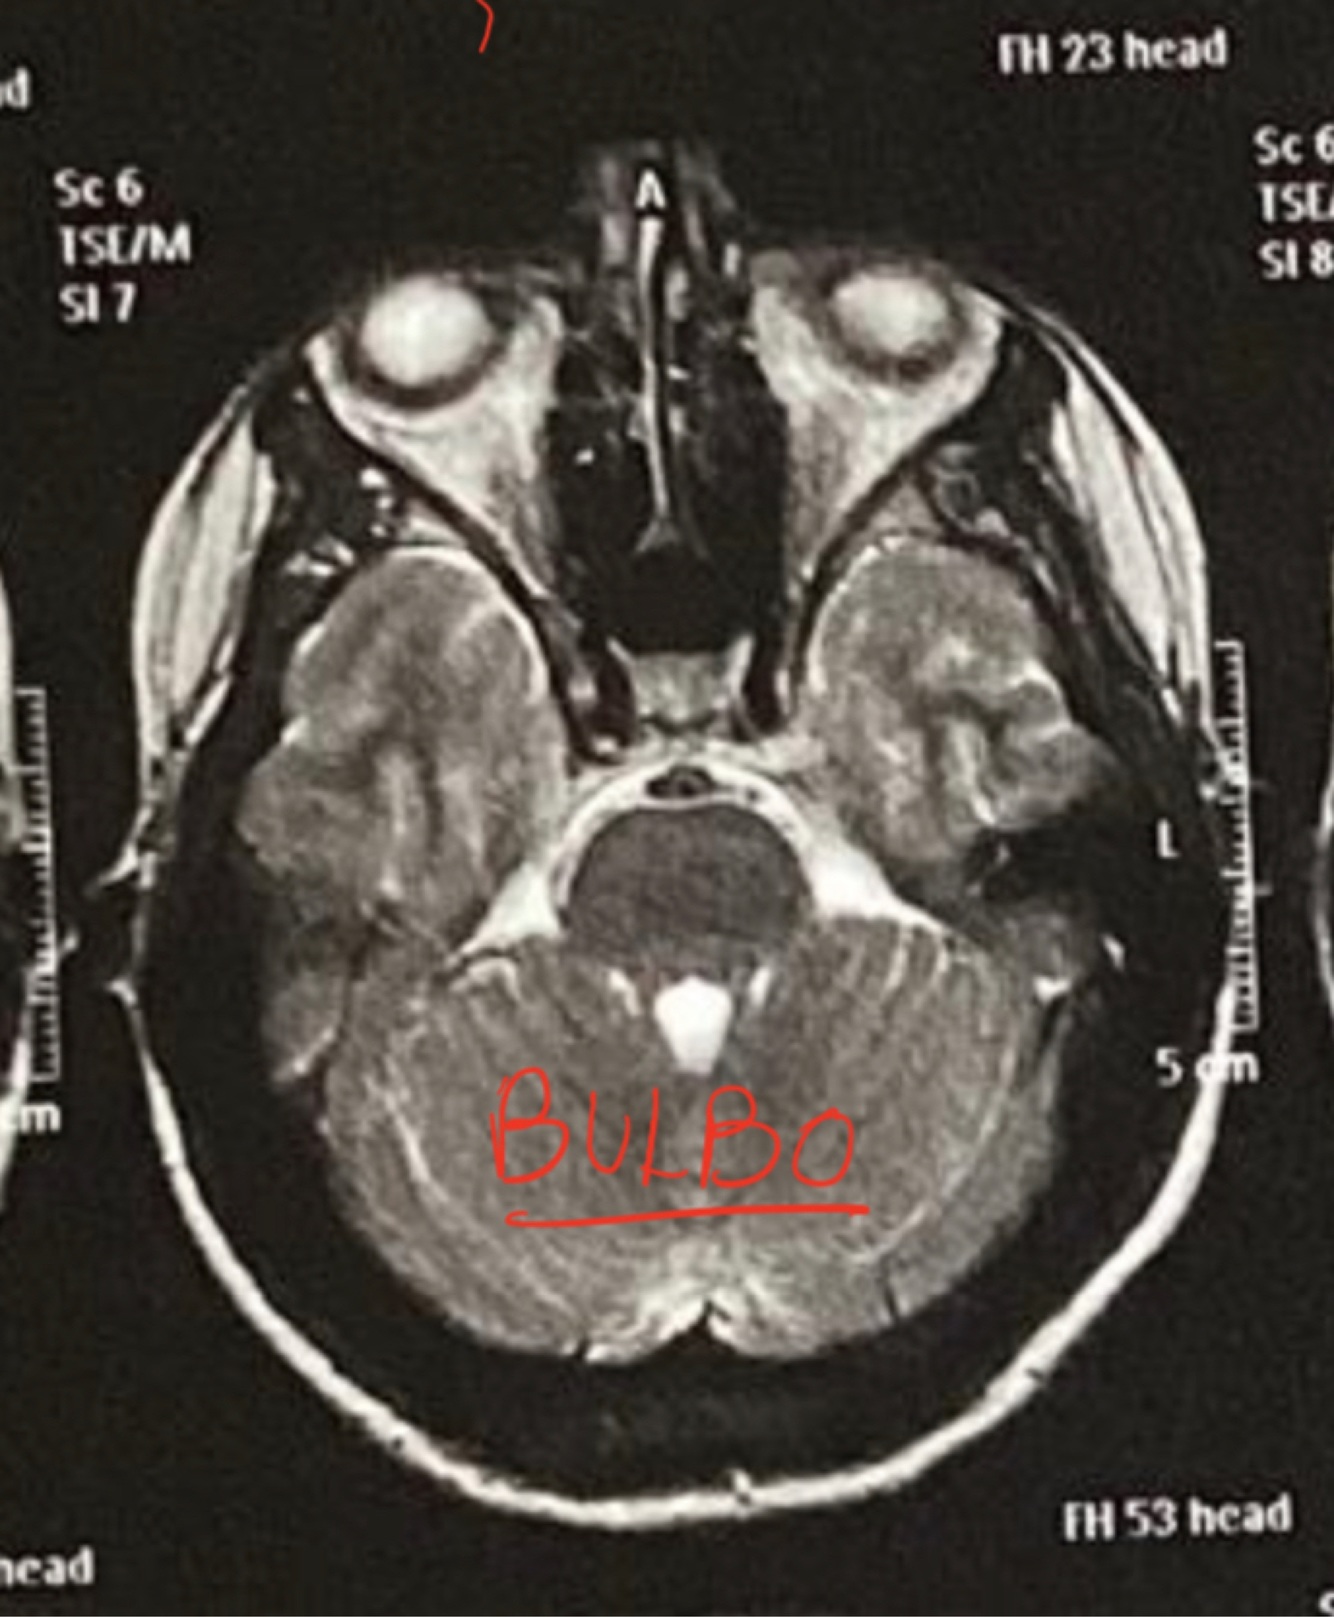

RM Axial Bulbo

A

Michey